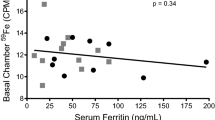

Seven PK studies were performed on four patients. Their therapy and QA values are listed in Table 1.The CSF EPO concentrations reflected the serum EPO levels and the permeability of the BBB (Fig.1A). The concentration of EPO in the CSF increased in all four patients after 1–3 h, peaked after approximately 24 h and declined bi-exponentially thereafter with similar terminal slopes in serum and CSF (Table 2). The serum and CSF EPO concentration-time profiles after administration of three EPO doses reflected the IV dosing schedule (Fig.1B). The EPO concentration in CSF peaked 4–10 h after each dose.

A Predicted (solid line) and observed concentrations of erythropoietin (EPO) in serum (circles) or cerebrospinal fluid (CSF) (triangles) in patient 1 who received a single 667 IU/kg (open symbols) and 1,500 IU/kg (closed symbols) IV doses and in patients 2, 3 and 4 who received a single 1,500 IU/kg IV dose of Eprex. B Predicted (solid line) and observed concentrations of EPO in serum (circles) or CSF (triangles) in patient 2 who received three 500 IU/kg (40,000 IU) Eprex doses every 24 h and in patient 4 who received three 667 IU/kg (40,000 IU) Eprex doses every 24 h

The EPO levels observed in the CSF appeared to depend on both the serum concentration of EPO and the permeability of the BBB as measured by the QA. The first-order distribution kinetics suggest that single rather than split IV doses are preferable to achieve a rapid rise of EPO in the CSF. The Cmax was approximately two to three times greater after one 1,500-IU/kg dose than after three daily doses of 500–667 IU/kg in patients 2 and 4 (Table 2).

Compartmental and non-compartmental analyses identified the serum concentration of EPO and the QA as the two principal determinants for the EPO concentration-time profile in the CSF. Using these two variables, we constructed a PK model with the assumptions described in the methods (Fig.2A). The estimated parameters for the PK model are listed in Fig.2B. The predicted concentration-time profiles of EPO in serum and CSF are based on the estimated model parameters and are shown as the solid lines in Fig.1A. For patient 1, the predicted concentration-time profiles in serum and CSF for the lower IV dose of 667 IU/kg are based on the model parameters estimated from the higher IV dose of 1,500 IU/kg in the same patient. There was a close agreement between the predicted profiles and observed data, suggesting that this PK model accurately describes the disposition kinetics of EPO in serum and CSF.